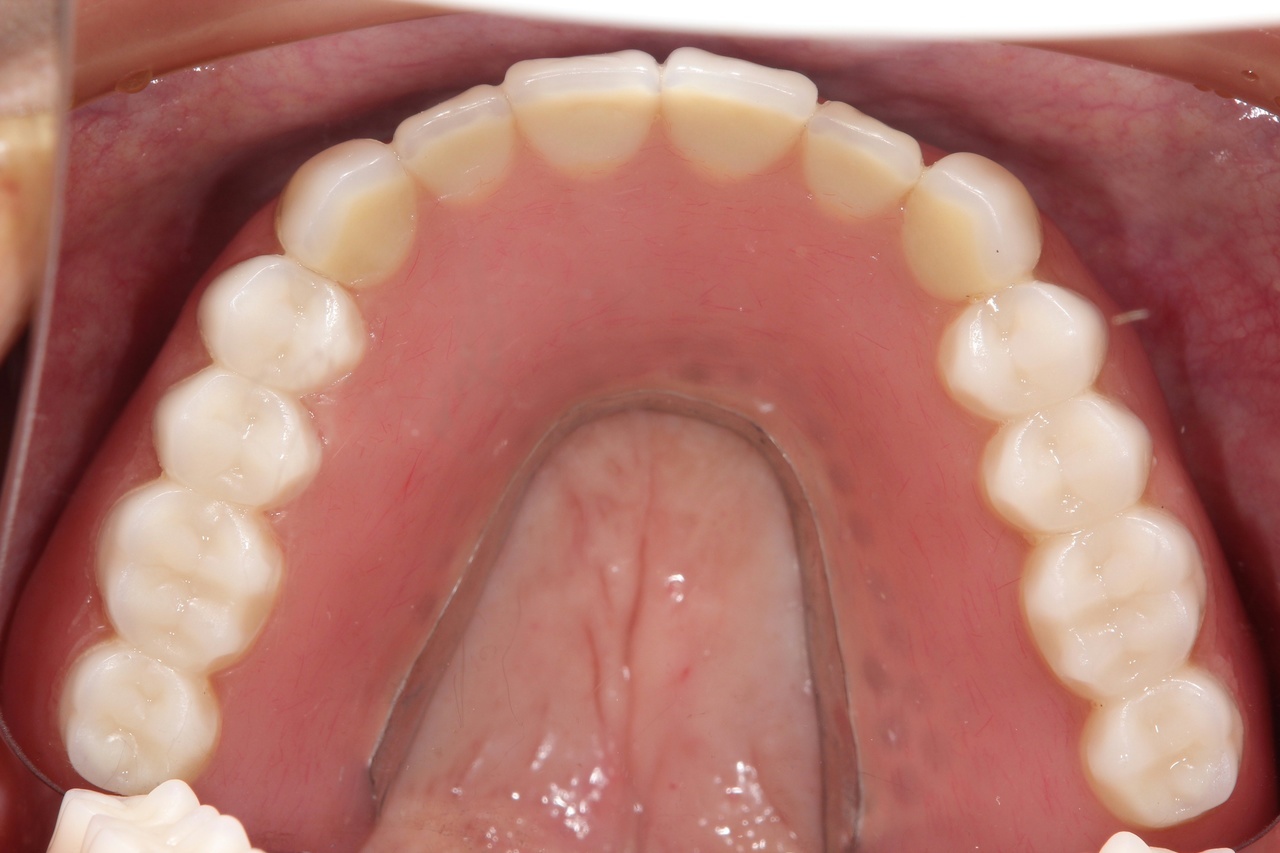

7本のインプラントで、12本の歯を並べる(上顎・仮歯代含む)

(御殿場市在住 男性)

お口の中の状態

レントゲン写真

7本のインプラントを埋入し、12本の歯を並べています。面長で奥行きが長い顔の方の場合、前歯部に1本インプラントを追加することで、咬合の安定を図ります。